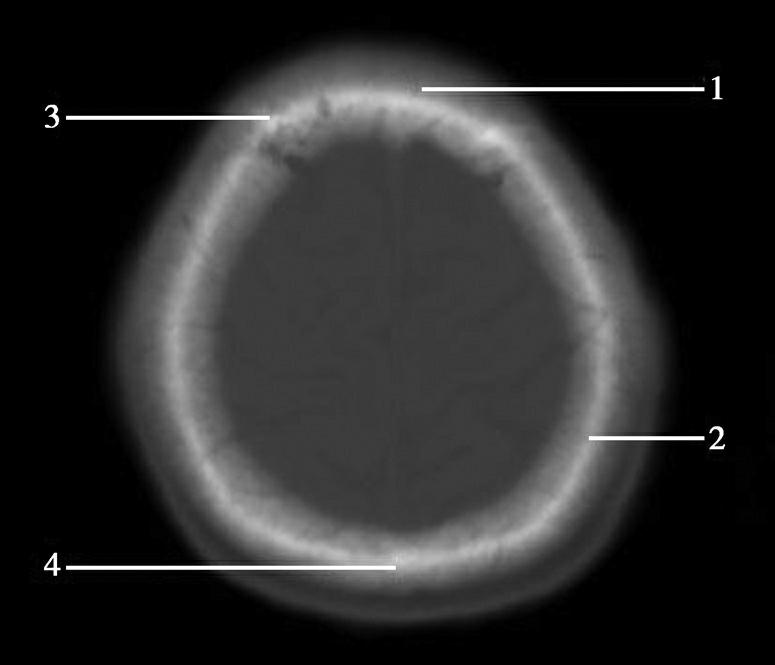

蝶骨体占据层面中部,内部可见蝶窦,中间有骨性分隔。蝶骨体前方正中为鼻中隔,鼻中隔两侧为蜂窝状含气骨性腔隙,即筛窦,筛窦前方为鼻骨。筛窦两侧可见两侧对称的圆形眼球断面位于眼眶内,眼球壁呈厚薄均匀的环状,称为眼环。玻璃体位于眼环内呈均匀低密度影,晶状体位于玻璃体前方,呈双凸透镜状高密度影,眼球后方为锥体形的眶脂体,其内正中可见视神经通行,眶内侧壁与筛窦间隔以菲薄的纸板,眶外侧壁由额骨眶突和蝶骨大翼构成,内、外直肌紧贴眶壁走向眶尖,视神经管位于眶尖。位于蝶窦两侧的有颞叶、颞骨鳞部及颞骨外侧的颞肌。蝶窦后方为斜坡,斜坡后外侧为颞骨岩部尖,后外方为乳突,其内可见乳突小房呈蜂窝状,岩部的内后缘可见两侧对称的内听道,其内第Ⅶ、Ⅷ对脑神经CT上无法分辨,听神经瘤常伴有内听道的扩大(图1-2-8)。内听道后外方的骨性空腔为中耳鼓室。枕骨斜坡及岩骨后方为颅后窝,脑桥位于其前部,脑桥后方可见第四脑室,其后方为小脑蚓部。小脑半球以小脑中脚与脑桥相连,脑桥与斜坡之间为桥前池,其向两侧延伸的部分呈三角形,两侧对称,位于脑桥、小脑中脚及岩骨之间,称为脑桥小脑角池。位于脑桥小脑角池的常见病变有听神经瘤、三叉神经瘤、脑膜瘤和胆脂瘤等(图1-2-9)。